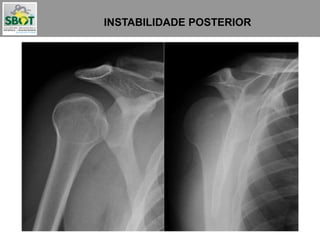

INSTABILIDADE POSTERIOR

Podem passar despercebidas

em até 50% das vezes

Podem passar

despercebidas em

até 50% das vezes

Ântero-medial:

Lesão de McLaughlin